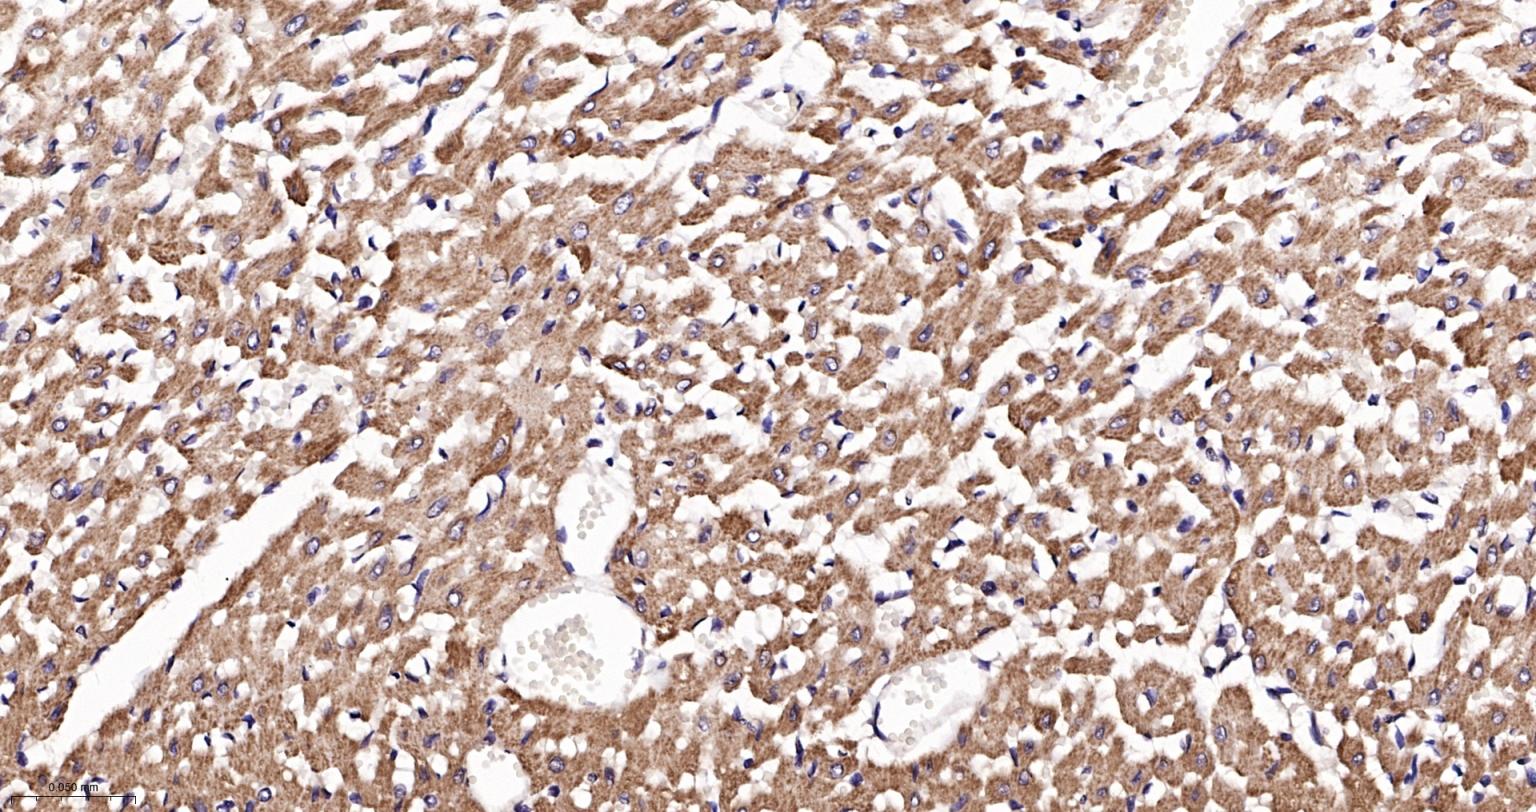

Paraformaldehyde-fixed, paraffin embedded Human Heart; Antigen retrieval by boiling in sodium citrate buffer (pH6.0) for 15 min; The section was incubated with AKT1 Monoclonal Antibody, Unconjugated (bsm-52010R) at 1:200 overnight at 4°C, followed by conjugation to the bs-0295G-HRP and DAB (C-0010) staining.

Paraformaldehyde-fixed, paraffin embedded Rat Heart; Antigen retrieval by boiling in sodium citrate buffer (pH6.0) for 15 min; The section was incubated with AKT1 Monoclonal Antibody, Unconjugated (bsm-52010R) at 1:200 overnight at 4°C, followed by conjugation to the bs-0295G-HRP and DAB (C-0010) staining.

Paraformaldehyde-fixed, paraffin embedded Human Kidney; Antigen retrieval by boiling in sodium citrate buffer (pH6.0) for 15 min; The section was incubated with AKT1 Monoclonal Antibody, Unconjugated (bsm-52010R) at 1:200 overnight at 4°C, followed by conjugation to the bs-0295G-HRP and DAB (C-0010) staining.

Paraformaldehyde-fixed, paraffin embedded Rat Kidney; Antigen retrieval by boiling in sodium citrate buffer (pH6.0) for 15 min; The section was incubated with AKT1 Monoclonal Antibody, Unconjugated (bsm-52010R) at 1:200 overnight at 4°C, followed by conjugation to the bs-0295G-HRP and DAB (C-0010) staining.

Paraformaldehyde-fixed, paraffin embedded Mouse Kidney; Antigen retrieval by boiling in sodium citrate buffer (pH6.0) for 15 min; The section was incubated with AKT1 Monoclonal Antibody, Unconjugated (bsm-52010R) at 1:200 overnight at 4°C, followed by conjugation to the bs-0295G-HRP and DAB (C-0010) staining.

Paraformaldehyde-fixed, paraffin embedded Human Breast Cancer; Antigen retrieval by boiling in sodium citrate buffer (pH6.0) for 15 min; Antibody incubation with AKT1 Monoclonal Antibody, Unconjugated(bsm-52010R) at 1:200 overnight at 4°C, followed by conjugation to the SP Kit (Rabbit, SP-0023) and DAB (C-0010) staining.

Paraformaldehyde-fixed, paraffin embedded Human Cerebrum; Antigen retrieval by boiling in sodium citrate buffer (pH6.0) for 15 min; Antibody incubation with AKT1 Monoclonal Antibody, Unconjugated(bsm-52010R) at 1:200 overnight at 4°C, followed by conjugation to the SP Kit (Rabbit, SP-0023) and DAB (C-0010) staining.